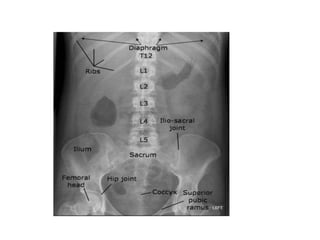

Normal Anatomy

1, 11th rib.

2, Vertebral body (TH

12).

3, Gas in stomach.

4, Gas in colon (splenic

flexure).

5, Gas in transverse

colon.

6, Gas in sigmoid.

7, Sacrum.

8, Sacroiliac joint.

9, Femoral head.

10, Gas in cecum

11, Iliac crest.

12, Gas in colon (hepatic

13, Psoas margin.

????

1, 11th rib. 2,Vertebral body (TH 12). 3, Gas in stomach. 4, Gas in colon (splenic flexure). 5, Gas in transverse colon. 6, Gas in sigmoid. 7, Sacrum. 8, Sacroiliac joint. 9, Femoral head. 10, Gas in cecum 11, Iliac crest. 12, Gas in colon (hepatic flexure). 13, Psoas margin.

• Normal ossalstructures on a supine AP image.